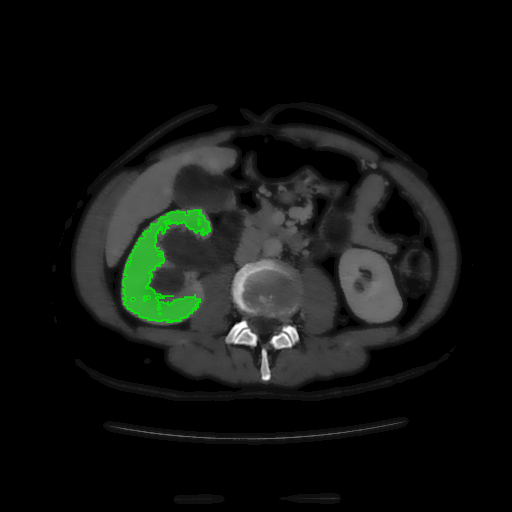

For MSER tracking, Donoser and Bischof [5] presented three different applications; license plate tracking, face tracking and the segmentation of a fiber network. In the third application, a fiber network is reconstructed in 3D by tracking a slice of the data along the axis orthogonal to the image data. Analogously, we track organs in slices of a Computed Tomography (CT) scan, to generate a 3D segmentation. We use the CT data provided in the 3DIRCADb dataset222The dataset is available on http://ircad.fr/research/3d-ircadb-01 [14].

To initialize the tracking process, the organ is segmented in an arbitrary slice of the CT data by a bounding box. The most stable MSHR is then selected in the initialization process for tracking. The respective MSHR is tracked through the slice data along the axis orthogonal to the image data. An example of the tracked regions is visualized for two examples in Fig. 7. Given the segmentations of the single slices, the organ can be reconstructed in 3D. We compare the reconstruction for MSER and MSHR tracking in Fig. 8. To enhance the visualization, the datapoints are triangulated and the surface normals calculated. Since the contrast of the organs can be very low in CT images, the MSER tracking has difficulties catching the organ boundaries. Furthermore, the organ is sometimes partely lighter and darker than the background, which may lead to MSER tracking failure. The proposed MSHR tracking copes well with these difficulties, and the reconstructions are significantly better.

Please note, the tracking of the regions in the CT slices is extremely efficient and only requires an average of 5ms per slice. Hence, for the 45 slices in Fig. 8 the complete 3D reconstruction process, which includes the triangulation (1sabsent1𝑠\approx 1s), the calculation of the surface normals (130msabsent130𝑚𝑠\approx 130ms), and the segmentation (220msabsent220𝑚𝑠\approx 220ms), requires only around 1.5s.

Figure 7: Two examples sequences from the 3DIRCADb dataset [14]. Given an initial selection of a single slice (the middle image in (a) and (b)) of the organ, the proposed MSHR tracking tracks the region forward and backwards in space. The segmented slices can be used to reconstruct the organ, see Fig. 8 for an example reconstruction.